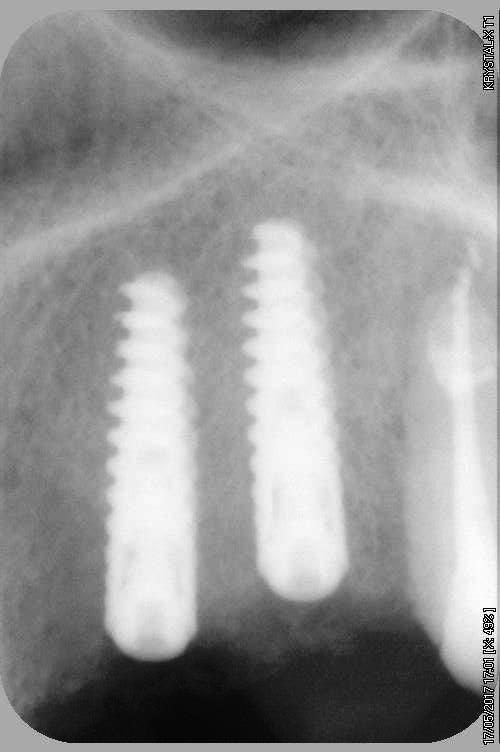

petit cas sympa ancien bridge très mobile....plutôt que d'extraire 25, j'ai déposé la couronne, retraité la dent stabilisation pendant deux mois puis séance d'ostéotension et ce jour pose de deux axioms PX 34120 après expansion...

comme je n'ai pas fait de décharges osseuse en vestibulaire, j'ai effectivement travaillé toute la longueur de la crête, mais, là j'ai ôtè les expanseurs avant de visser les implants car ce sont des PX qui ont un apex assez fin, pour des regular j'aurais pratiqué différemment.

par contre je suis passé par le stade implants lisse (34100 et 34120)

par contre les axioms doivent être posé en sous crestal, ce qui est fait ici, avec sans doute comme souvent une nécessitè d’ostéotomie, lors de la mise en charge, car il est fréquent que le col implantaire soit recouvert.